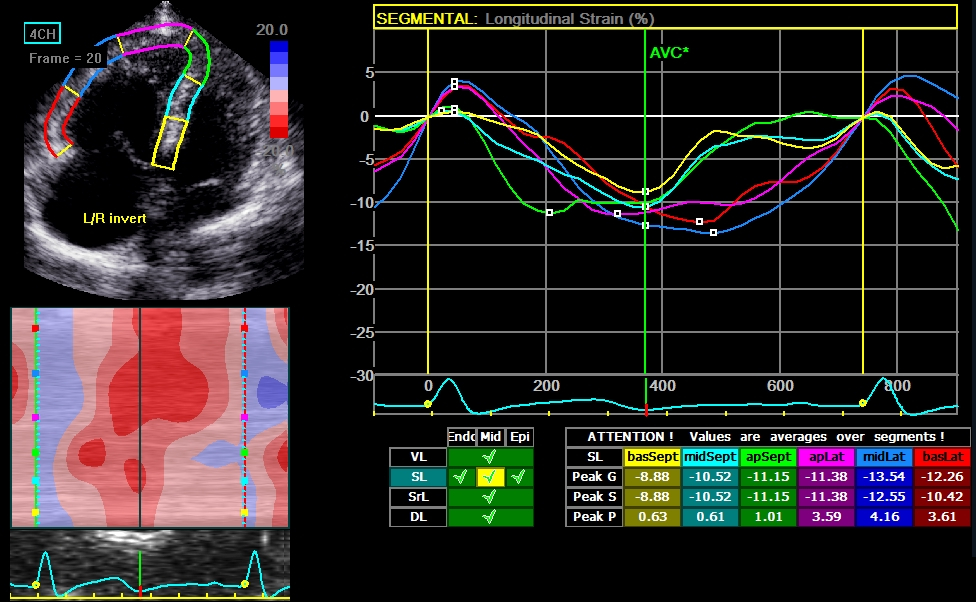

Methods: From April 2017 to March 2018, PcPH patients at Fuwai Hospital were consecutively enrolled. They were grouped as low-risk and non-low-risk according to 2015 European Society of Cardiology Guidelines. RV mechanical dyssynchrony (RV-SD6) was measured by off-line software (GE EchoPAC version 201), and QRS duration representing electrical dyssynchrony was manually measured.

Results: Sixty-six PcPH patients (average 35 years, 19 males and 47 females) were finally enrolled, 37 in low-risk group, while 29 in non-low-risk group. QRS duration was significantly correlated with RV-SD6 (r = 0.25, P = 0.047). Both RV-SD6 and QRS duration significantly correlated with N-terminal pro-brain natriuretic peptide (r = 0.44, P<0.001 vs r = 0.26, P = 0.039). Furthermore, RV-SD6 (area under curve, AUC 0.75, 95% confidence interval, CI 0.64–0.87, P < 0.001) and QRS duration (AUC 0.65, 95% CI 0.52–0.78, P = 0.036) both had the potential to predict non-low risk stratification. Multivariate Logistic regression analyses identified RV-SD6 (OR: 1.02, 95% CI: 1.01–1.03, P = 0.009) and QRS duration (odds ratio, OR: 1.07, 95% CI: 1.00–1.15, P = 0.045) as independent predictors of non-low risk of PcPH patients.

Conclusion: RV-SD6-presented mechanical dyssynchrony correlates with QRS duration and better predicts risk stratification in PcPH patients without complete bundle branch block.